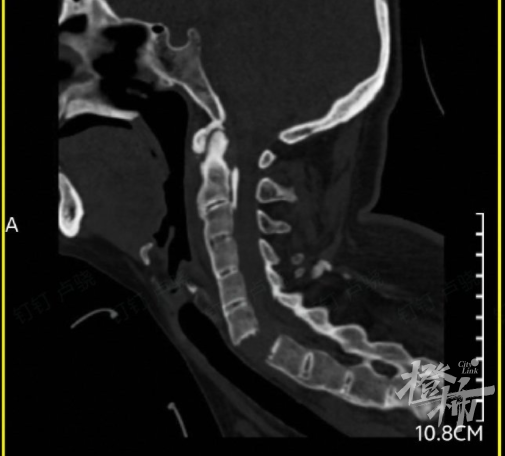

(检查发现,刘女士的颈椎完全断离)

当时,刘女士就出现颈部疼痛、四肢无力的症状,紧接着发现自己全身不能活动。随后,她被紧急送往附近的医院救治,通过颈椎影像检查后发现,刘女士颈椎6-7节完全断离,颈椎骨折造成脊髓损伤,导致全身瘫痪。